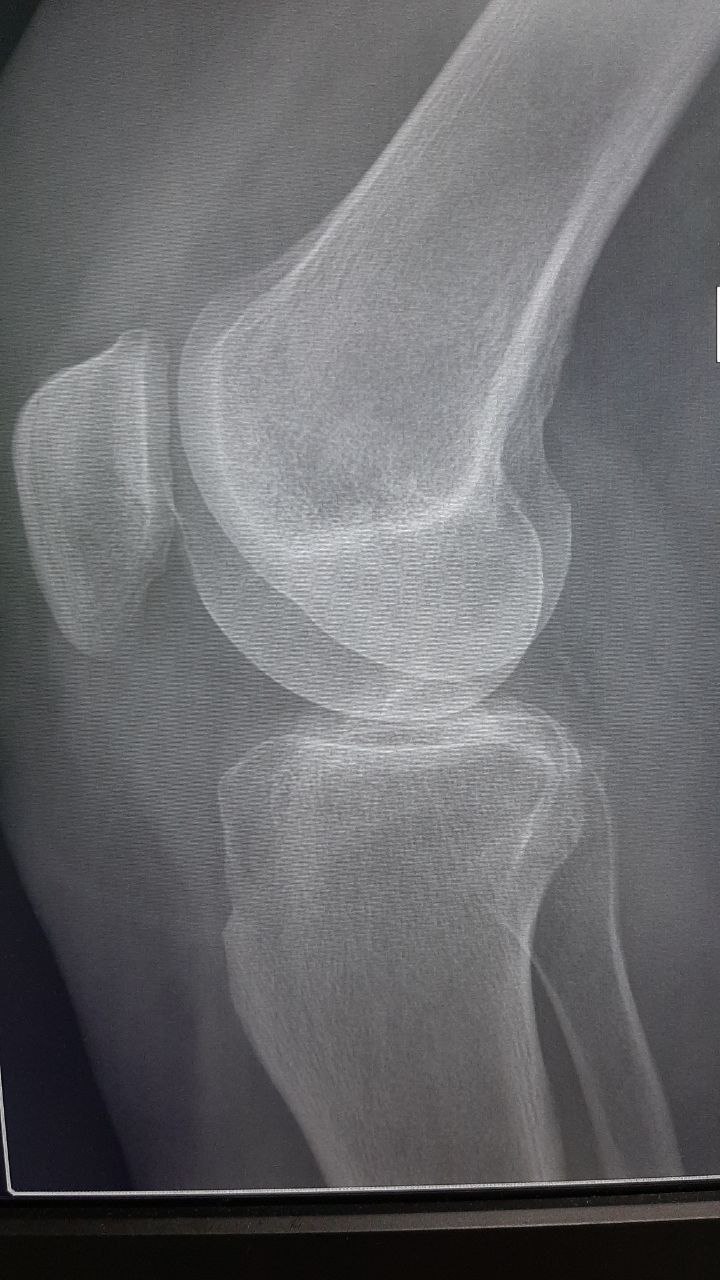

👆Для тех, кто разбирается в снимках, это мои снимки, сделанные в марте текущего года, с диагнозом гонартроз коленного сустава. Те, кто столкнулся с этим заболеванием, прекрасно понимают, какие мучительные боли могут сопровождать каждый день, и даже ночь. Необходимость носить наколенник, а в качестве лечения — только уколы или даже операция… Знакомо?

Артроз колена, или гонартроз, действительно коварен. Одной из главных проблем является постепенное истончение и ослабление костной ткани. На моих снимках отчетливо видны признаки истончения костей, неровности и повреждения хрящевой ткани. Я предпринимала попытки растягивать мышцы передней и задней поверхности бедра, которые поддерживают коленную чашечку, но, к сожалению, делала это нерегулярно.